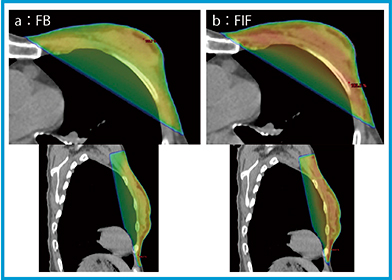

Halcyonの乳房の接線照射において,FBを用いて治療計画を作成した場合にも高線量域が出現するケースがあり,このような場合にはISCもしくはfield in field(FIF)の使用を推奨する。少しの工夫で通常のリニアックによる治療計画と遜色ない線量分布が作成できる。ここではFIFを例に挙げ,FBとの比較を示した(図4)。また,鎖骨上窩リンパ節を含む乳房の接線照射にて,尾側方向に3cmアイソセンタをシフトさせた際の治療計画を作成した(図5)。治療計画上の線量分布は「TrueBeam」(バリアン社製)と同等であり,鎖骨上窩リンパ節と乳房の照射野接合部に高線量域は生じていない。フィルムによるQAを実施し,hot spotなどの問題がないことは確認ずみである。

図4 Halcyonによる乳房の線量分布

a:FB max:109.8%,min:92.2%,mean:101.3%,MU:272.6 /279.8

b:FIF max:102.8%,min:89.3%,mean:97.6%,MU:248.0(infield 17.9)/254.5(infield 18.5)